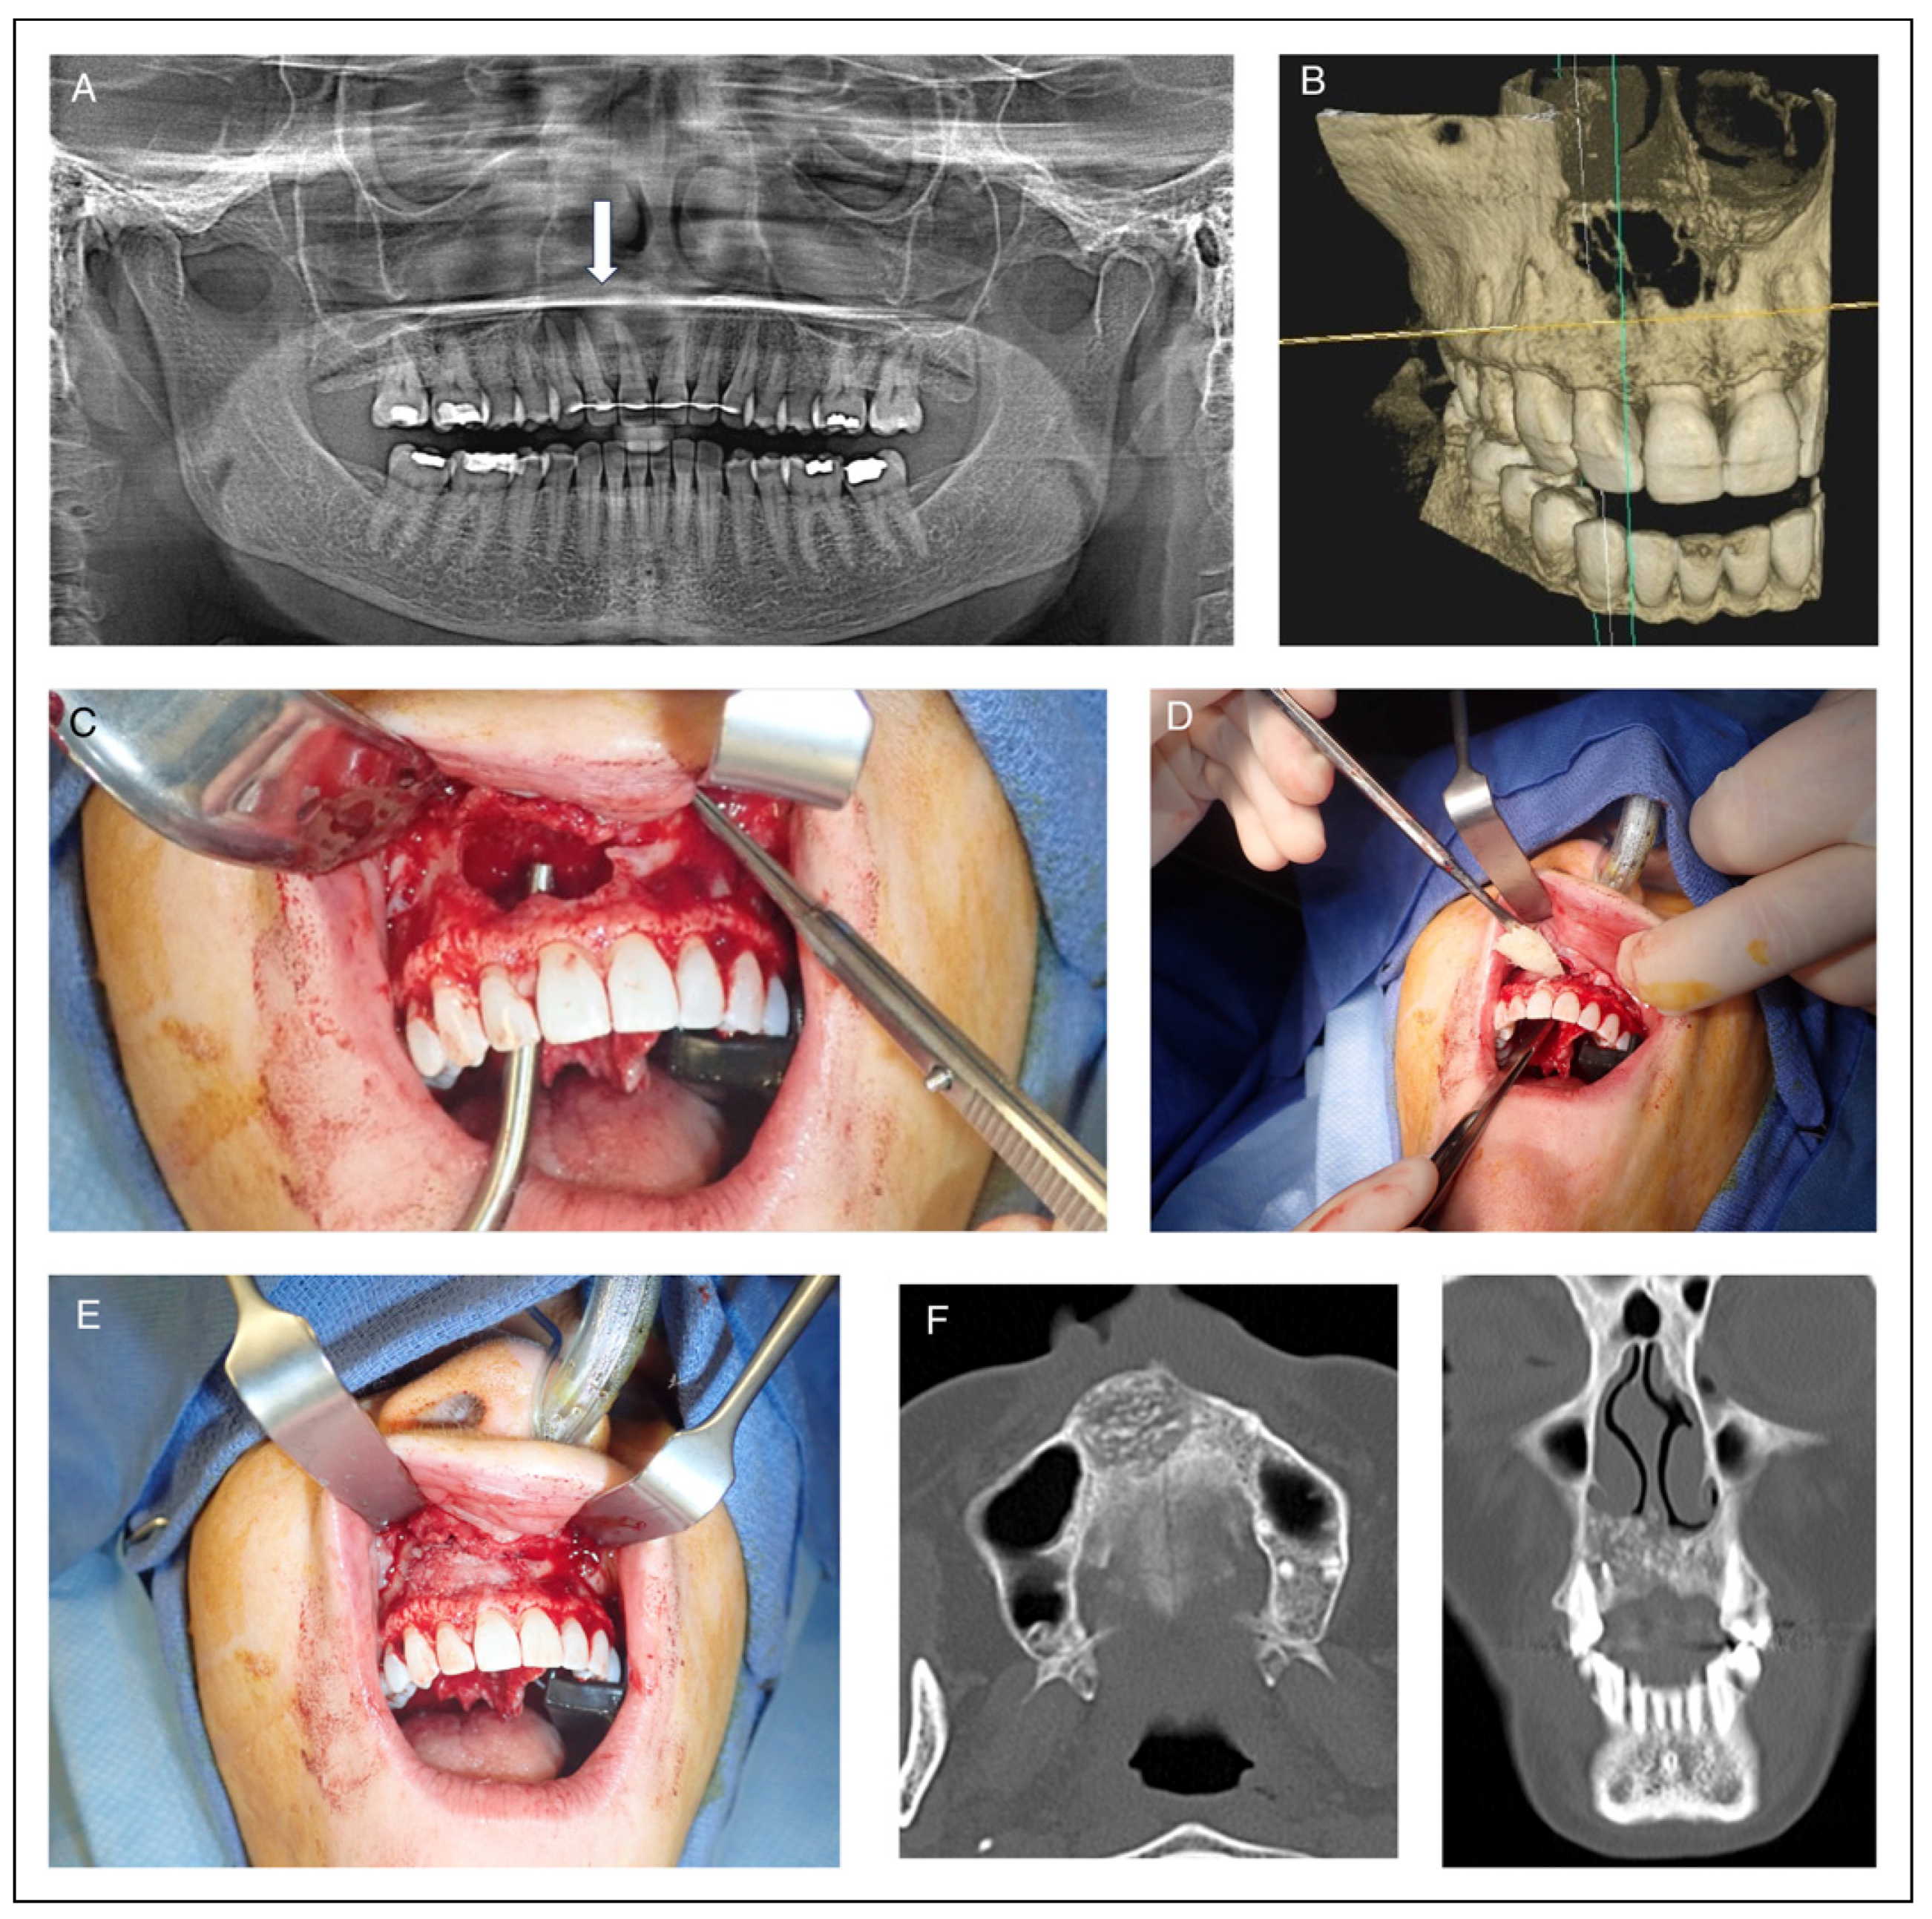

Reconstruction of Maxillary Bone Defects with Cellular Bone Matrix Allografts

Methods

Study Design and Sample

Results